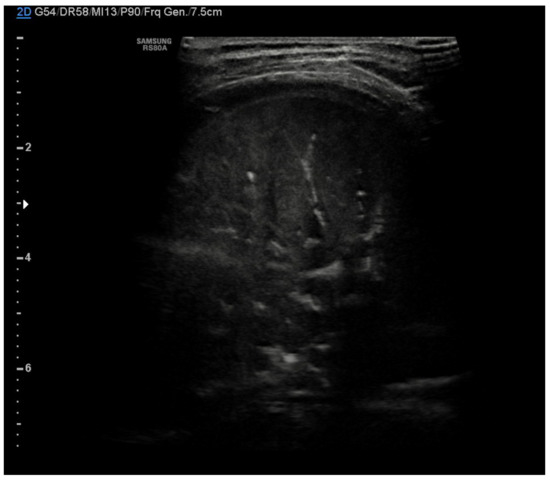

Neonatal respiratory distress syndrome (NRDS) is characterized by a functional and structural immaturity of the lung resulting in respiratory distress that appears at birth. The ultrasound findings of NRDS are represented by coalescent B-lines, diffuse and symmetrically distributed in both lungs. These lines are due to the presence of fluid in the interstitial or alveolar compartment, and generally, their number correlates with the severity of the disease, up to “white lung” in the most severe cases. The pleural line appears irregular, poorly defined and thickened. In addition, small areas of hypoechogenic subpleural consolidation can often be observed, especially in the posterior lung fields (Figure 4) [21].

Figure 4.

Neonatal respiratory distress syndrome (NRDS). Coalescent B-lines, irregularity of the pleural line and subpleural consolidation are visible.